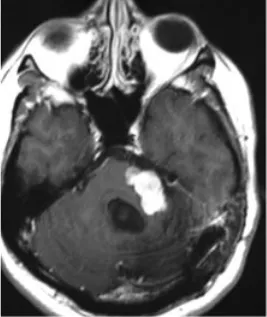

然而恶化的速度远超预期。根治性切除手术后不过三个月,肿瘤即以极强的侵袭性迅速复发,并对脑干造成严重压迫。为维系基本生命功能,患者紧急接受了第二次手术以实施脑干减压。这一次的病理结果表明,肿瘤已进一步去分化,转化为间变性软组织肉瘤,神经源性标记物S100蛋白的表达已完全丧失。

最终结局与临床警示

在计划启动辅助放疗的等待期内,肿瘤在短短四周之内再度复发。疾病的恶性程度与增殖速度,已超出现有所有治疗手段所能干预的时间窗口。末次手术后一个月,残余肿瘤再次侵袭性生长,对脑干造成致命性压迫,患者最终离世。